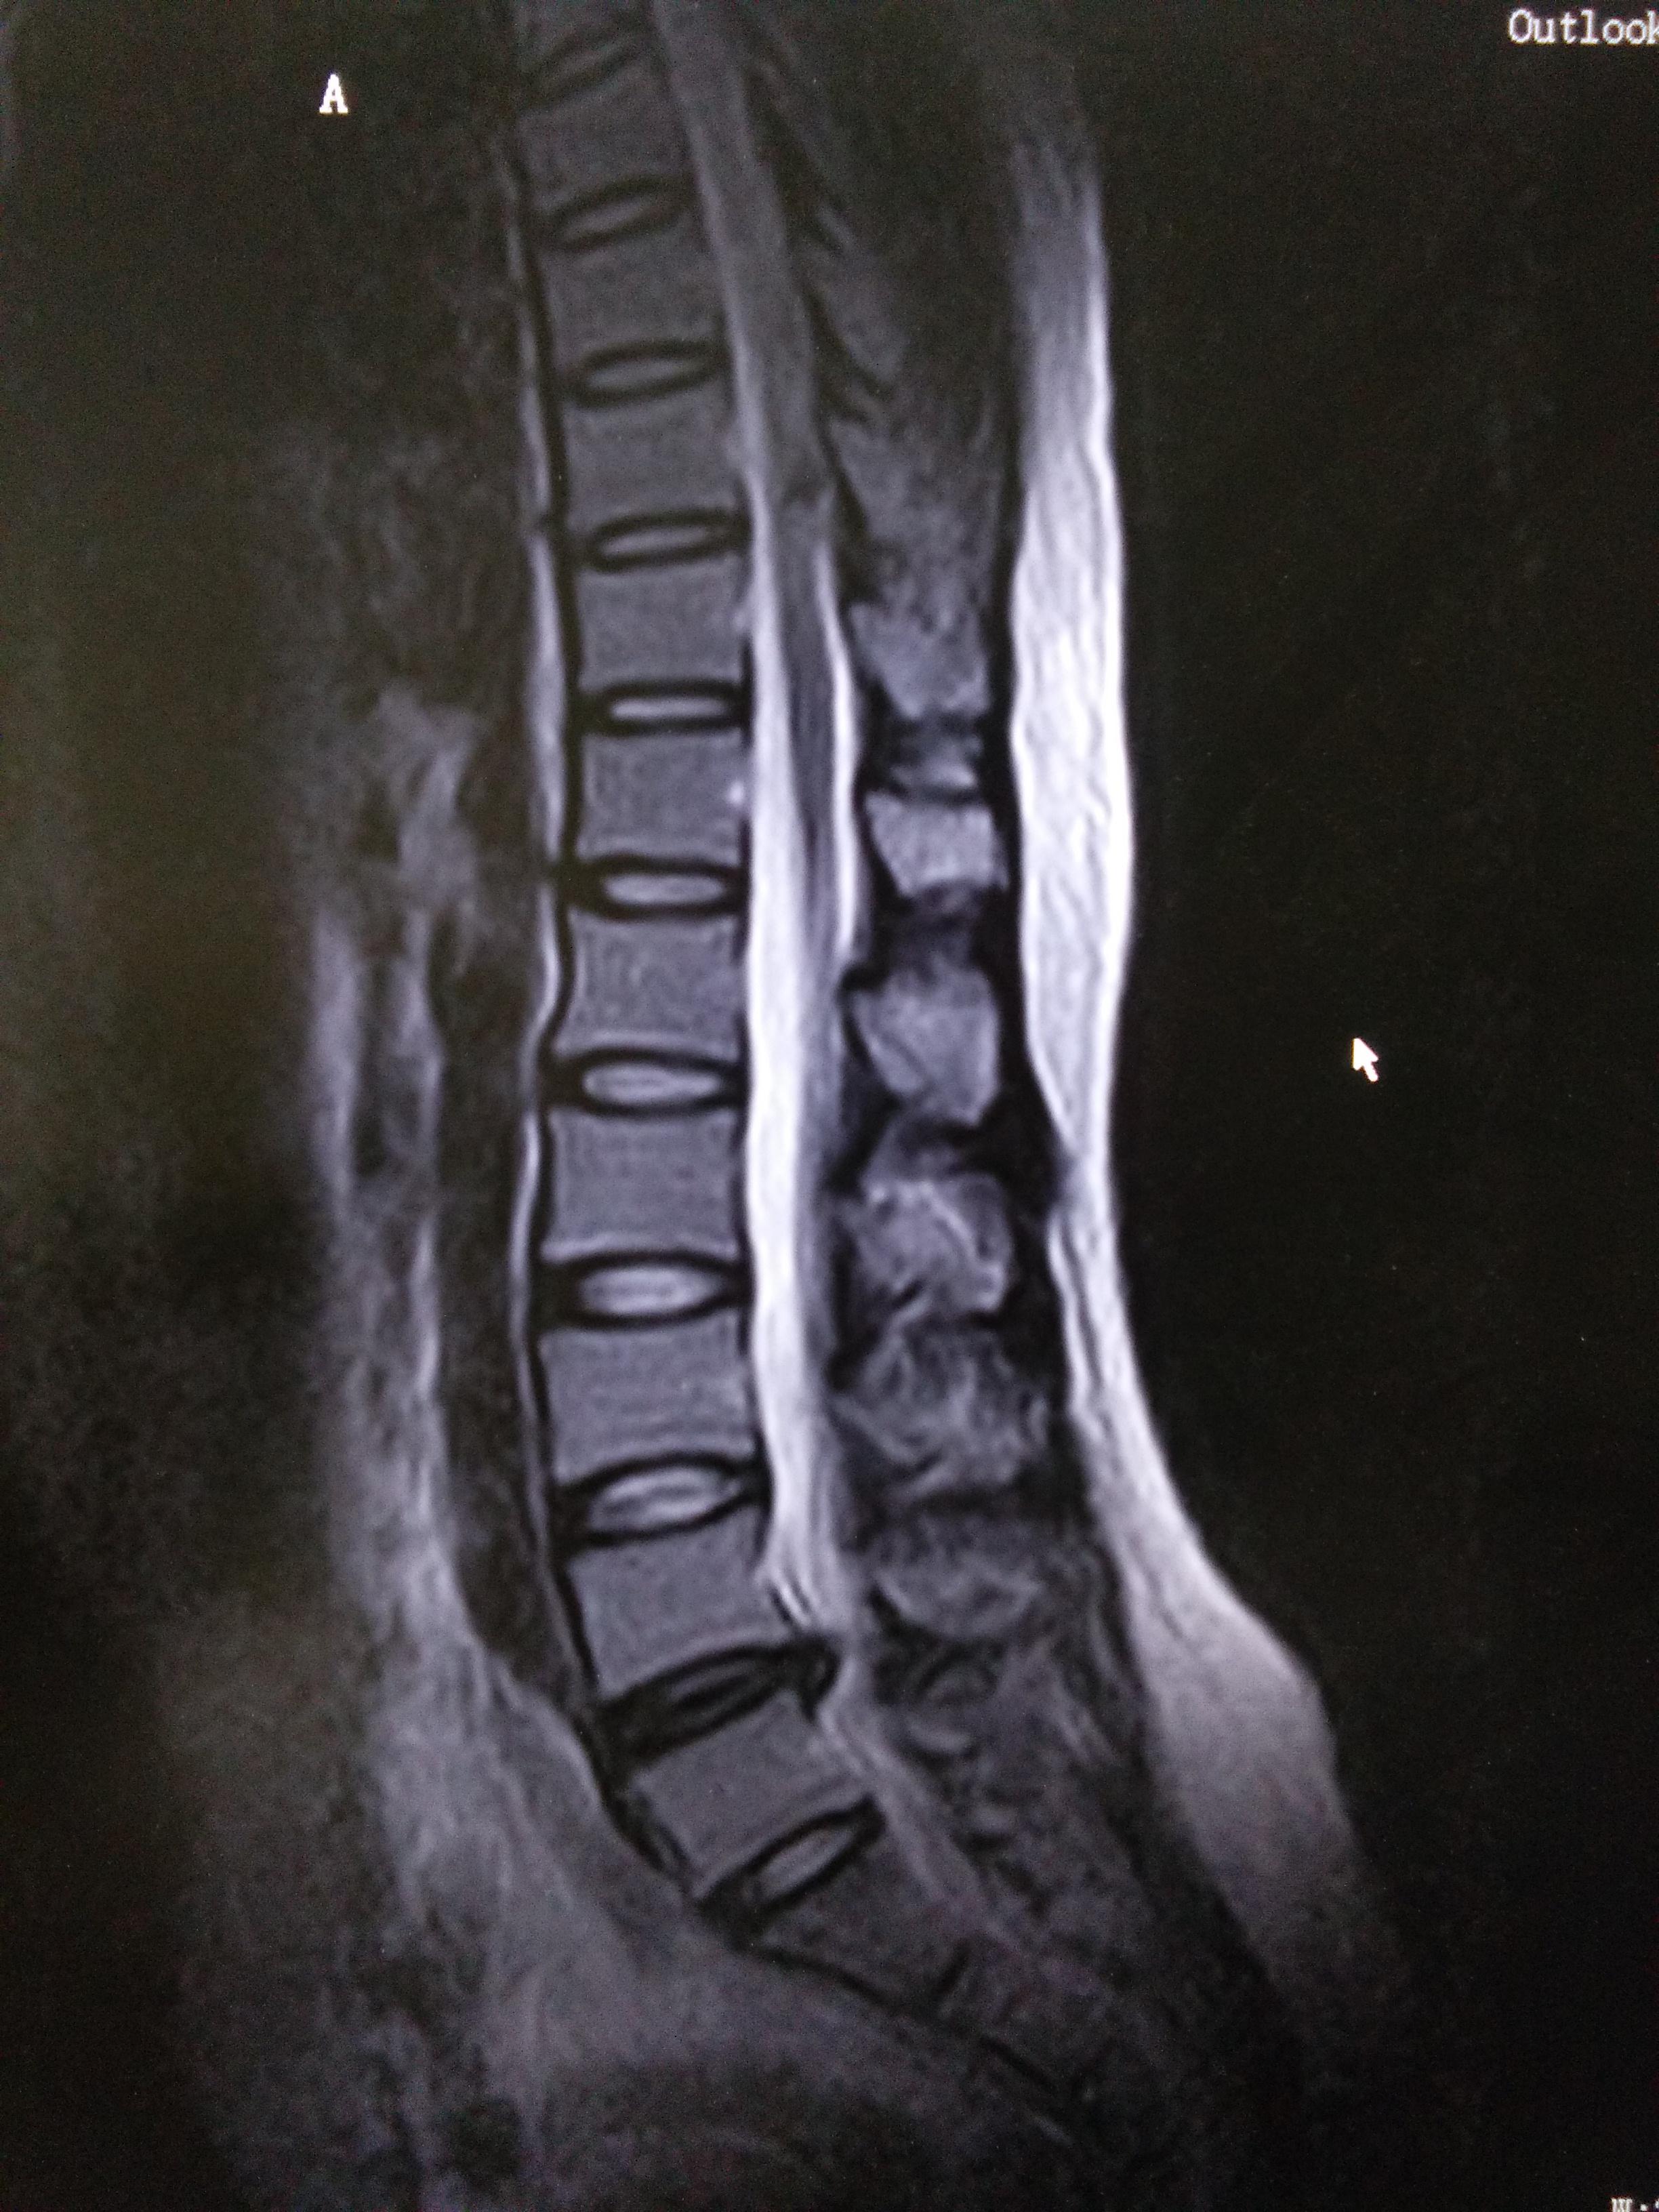

摘要:三天快速緩解腰間盤問題的方法包括休息、物理治療及適度運動。首先需充分休息,避免過度活動;其次可進行熱敷、按摩等物理療法減輕疼痛;適度進行腰部鍛煉,如輕度伸展和強化肌肉,有助于改善腰間盤狀況。遵循這些方法,可有效緩解腰間盤問題帶來的不適。

腰間盤問題是一種常見的健康問題,可能導致疼痛、不適和活動受限,許多人尋求快速有效的解決方案以減輕癥狀,本文將介紹一種三天內(nèi)可以治好腰間盤問題的方法,幫助您緩解不適,恢復健康。